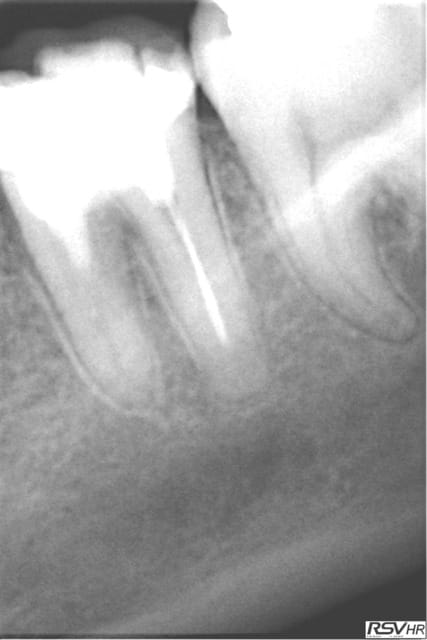

Un dernier pour la route legacy2 7mm

16 RTE 2006 /2007 avec curetage périapical et IRM

échec de cicatrisation et extraction-implantation le26.02.2011

empreinte essayage pose le 24.10.2011

radios de contrôle en 2012 et 2013

patiente revue en 2014 cbct =ok